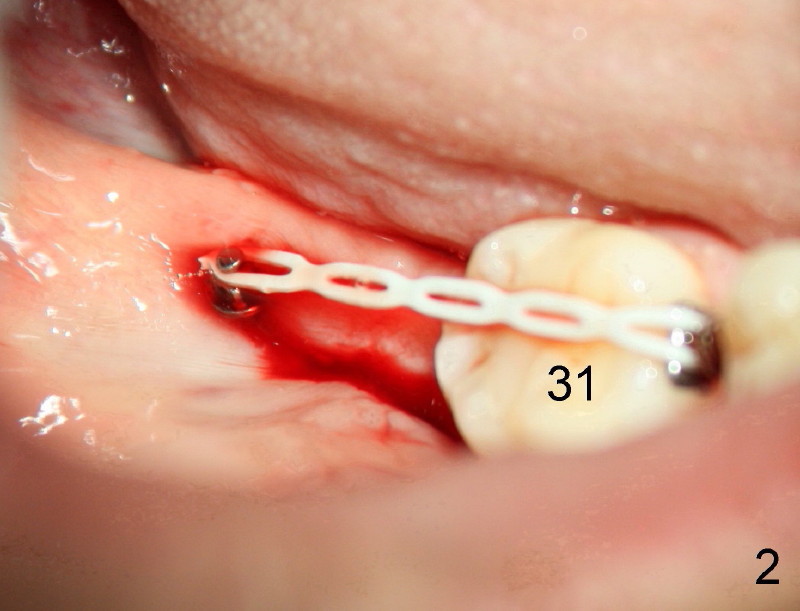

Small incision is made in the retromolar area. Pilot drill is used before a 10 mm Ancor Pro Mini-implant is placed (Orthoorganizer). But it is too loose. Incision is extended distally. With shallower pilot drilling, the next placement of mini is stable (Fig.2). With placement of lingual button on the mesial aspect of #31 and power chain (Fig.2,5), the journey of distalization begins. But it is not so easy as expected.

The good things about mini is that if mini does not catch the bone (stability), counter-rotate it, find a new spot and do it again until you hit home run (Fig.2). The wound heals uneventfully in spite of bloody field. Since the maxilla has spongy bone, pilot drilling is not required. The palatal root of the maxillary molar is narrower mesiodistally than buccal. Therefore, mini can be placed a little bit closer to the palatal root than buccal. The tip of mini is directed apically so that there is more room for placement.